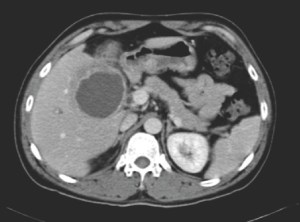

The same young man from Myanmar mentioned in Vignette 4 was extensively worked up for his fever. Blood cultures were negative. A CT of his abdomen, however, showed the following lesion in his liver.

The CT image shows a hypodense and rather regular structure in the liver. In this setting, the most likely diagnosis is amoebic liver abscess. There are a few ways to confirm this diagnosis, the simplest being a blood test for antibodies to Entamoeba histolytica – the causative organism. A biopsy of the wall of the abscess may also be performed under radiological guidance – amoeba can usually be seen on histopathology (but an aspirate of the pus is usually negative). Stool microscopy for amoebic cysts is not particularly helpful, as the test is not very sensitive (approximately 40% positive), and presence of the cysts is not conclusive proof that the abscess is caused by Entamoeba histolytica.